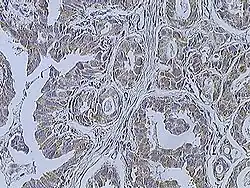

Histopathologic criteria

On microscopic evaluation carcinomatous cells are seen below the basement membrane of lactiferous ducts and invade into the surrounding breast stroma. Otherwise, there are no specific histologic characteristics, essentially making it a diagnosis of exclusion.[21] The histopathologic characteristics seen in these lesions are heterogenous. The cells of a lesion of invasive carcinoma NST may retain >70% ductal differentiation or appear completely undifferentiated. The tumor cells may be arranged in sheets, nests, cords, or singly distributed. They are pleomorphic (i.e., vary in size and shape). They usually have prominent nucleoli and multiple mitotic cells per magnified field of view, which are features generally consistent with cancerous cells. The surrounding non-ductal tissue, known as stroma, can range from none to abundant.[22][23]

Small inclusions of special features may be present within an invasive carcinoma NST tissue sample, but will be 'limited' (i.e. <10%). Carcinomas of mixed type will have a specialized pattern or lobular carcinoma in the majority (i.e. at least 50%) of the tumor and a non-specialized pattern in between 10 and 49% of the sample. Thus, such tumors will be called mixed invasive NST and special type or mixed invasive carcinoma NST and lobular carcinoma.[24]